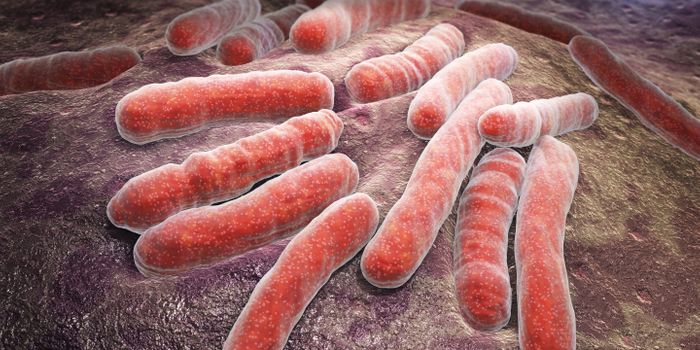

NOV 17, 2015MicrobiologyTuberculosis has been infecting humans for several millennia, making it one of the most horribly successful diseases in ...